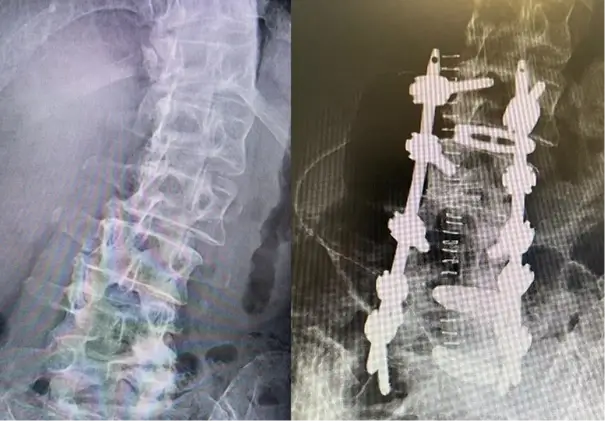

Case Report